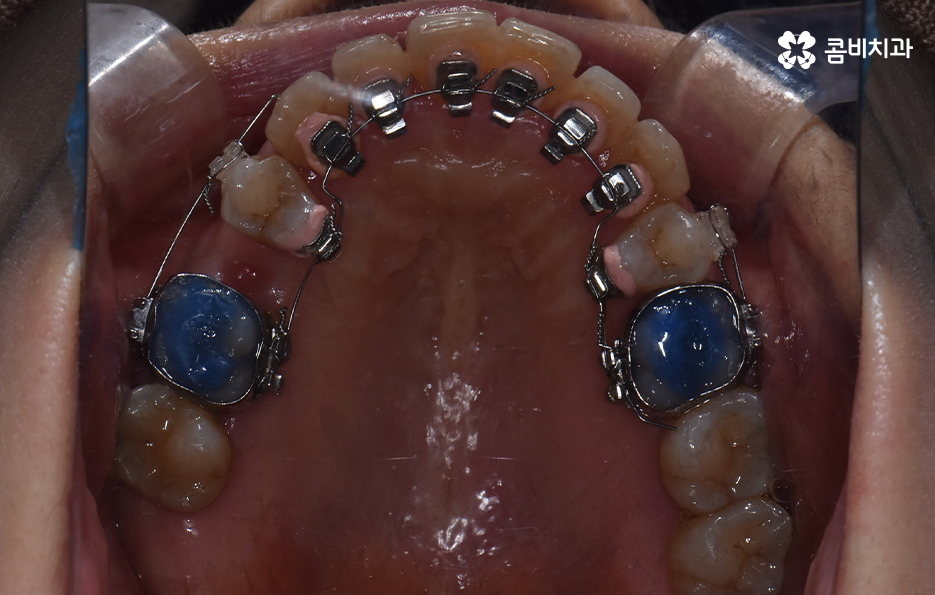

콤비교정은 윗니는 설측으로 진행하고 아랫니는 순측으로 교정기를 착용하기 때문에 웃을 때 주로 보이는 앞니는 교정기 착용이 티가 안난다는 점에서 크게 웃지 않는다면 교정기 착용이 거의 티가 안나는 수준으로 교정을 진행할 수 있어요

오늘 보시는 교정 사례의 경우를 보시면 아랫니의 틀어짐도 크지만 측면 사진으로 보시면 치열로 인해 돌출입에 영향을 준다는 사실도 알 수 있어요. 즉 치열과 함께 돌출입도 함께 고치고 싶어하기 때문에 치열도 재배열 하지만 치아 안쪽으로 넣어서 입술라인과 얼굴형으로 볼 때도 돌출입도 치료하는 치료 계획을 세웠기 때문에 작은 어금니 발치를 통한 치아의 이동 공간을 확보한 사례로 볼 수 있어요